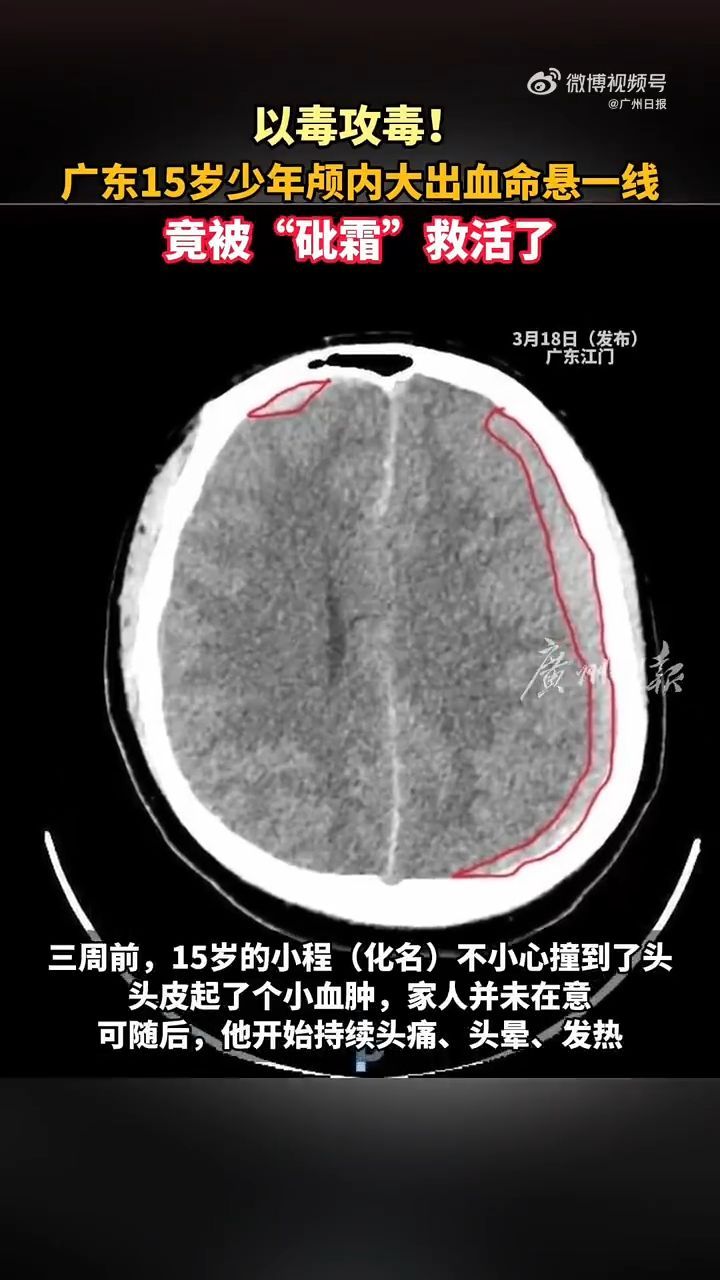

三周前,小程不小心撞到了头,头皮起了个小血肿,家人并未在意。可随后,他开始持续头痛、头晕、耳鸣,紧接着发热、呕吐接踵而至。到医院一查,结果令人震惊:白细胞飙升至65×10⁹/L,异常细胞疯狂增殖;血小板却骤降至16×10⁹/L,凝血功能全面崩溃;骨髓中大量“早幼粒细胞”异常增生;头颅CT显示:颅内大出血,血肿正在压迫大脑中枢。这不是磕碰惹的祸,而是一种极其凶险的白血病——M3,已经悄然引爆了“体内炸弹”。

入院第三天,小程开始出现烦躁、胡言乱语。复查CT显示:血肿扩大,脑组织受压,出现“大脑镰下疝”——这意味着,控制呼吸和心跳的脑干随时可能被压迫,导致呼吸心跳骤停。